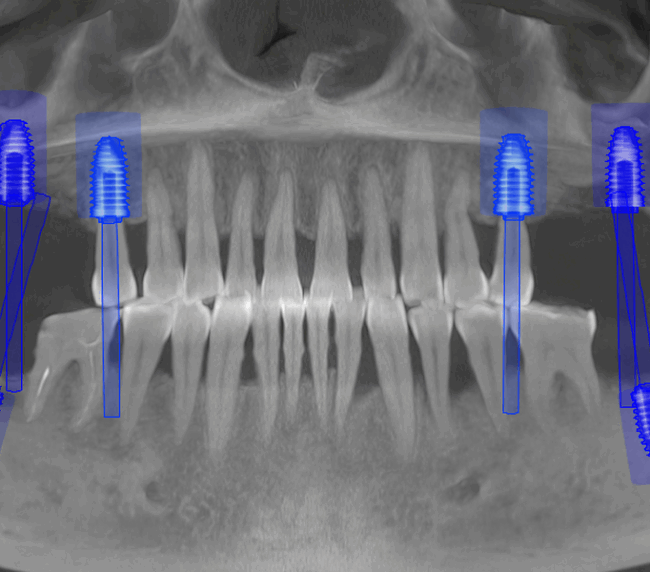

- Șlefuirea dinților de susținere sau inserarea implanturilor

- Tehnologie CAD/CAM și scanare digitală 3D